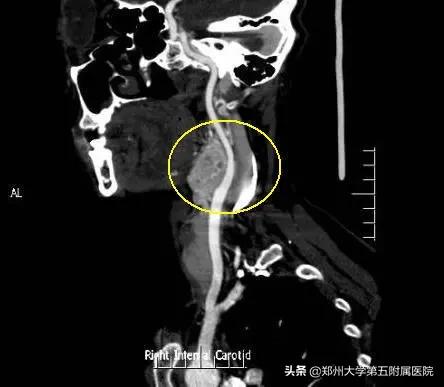

由于当地技术条件有限,无法进行手术切除。于是推荐赵女士到 郑州大学五附院血管外科诊治 。王兵教授、崔文军主任看过片子后,进一步给病人完善了检查确诊,尽管瘤体直径不大,但向上蔓延较深,手术切除非常棘手。

▲ 术前CTA右侧颈动脉局部占位